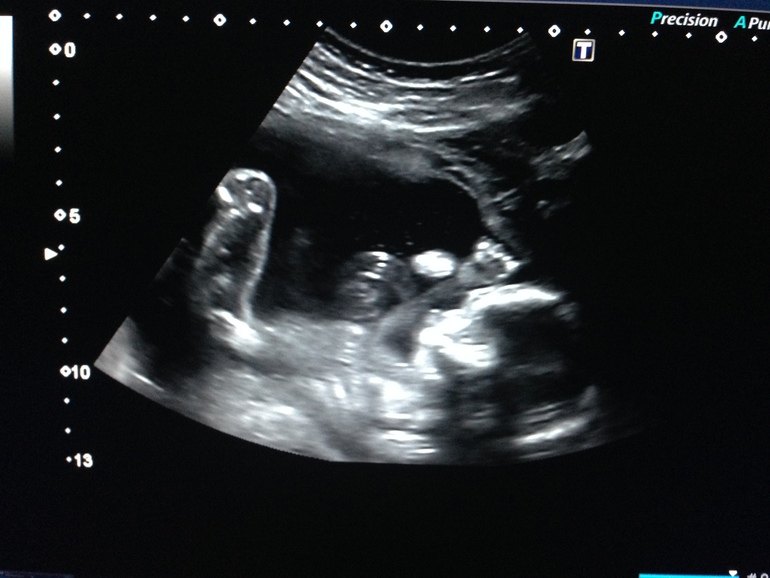

Разумеется, точно пересчитать малышей в вашем животе сможет только врач во время УЗИ (сделать его можно уже на 4–5-й неделе беременности).

Благодаря современным методам диагностики, многоплодная беременность определяется еще на ранних сроках. Во-первых, врач может диагностировать двойню при обычном осмотре – обратив внимание на быстрое увеличение размера матки или услышав двойное сердцебиение. Опытный специалист может диагностировать двойню уже после 4 недель беременности. Во-вторых, двойня диагностируется при УЗИ-осмотре. Обычно это происходит после 12 недель. До этого будущая мать может только предполагать, что носит двойню – например, опираясь на семейную историю и частые случаи рождения близнецов в семье. Анализы крови достоверным способом определить двойню пока не являются.

Для диагностики различных состояний, врачи часто используют УЗИ. Будущей маме предстоит регулярно проходить такое обследование. Именно этот метод позволит узнать, сколько малышей находится в матке. Стоит выяснить, когда можно определить двойню по УЗИ. Специалист может увидеть количество эмбрионов примерно в 5-6 недель. Но по разным причинам на маленьком сроке устанавливают, что в матке несколько плодов, не всегда. В ряде случаев врач точно диагностирует этот факт позже, например, во время скрининга в первом триместре.

- УЗИ на сроке 8-12 недель уже может показать присутствие двух или трех плодов. Но на таком сроке ошибка не исключается.

Самый точный способ подтвердить то, что у вас многоплодная беременность — узи диагностика. Этот метод позволяет на ранних сроках определить количество зародышей с точностью 99,3%.

Женщины с многоплодной беременностью должны быть под постоянным присмотром. Определить многоплодную беременность можно на УЗИ, также как при обычной беременности. На сроке в 5 недель на УЗИ можно увидеть, сколько малышей родится.

Многоплодная беременность на раннем сроке

Врач определяет двойню на УЗИ на 5 неделе. Провести исследование можно раньше, когда матка сильно увеличивается. При беременности двойней врачи назначают УЗИ один раз в месяц. Так им видно как развиваются малыши. На 5 неделе не удается определить пол или количество эмбрионов. Это может возникнуть из-за качества УЗИ.